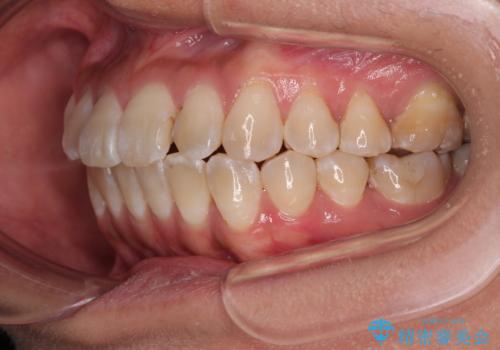

全く目立たないワイヤー矯正 上下裏側矯正

- 上下の前歯のでこぼこを気にして来院された患者様です。

職場の都合により、表側のワイヤー装置や着脱作業が頻繁なマウスピース矯正は困難とのことで、全く目立たない裏側矯正装置を用いて口元を整えることとしました。

途中転勤や出産があり、通院できない期間が長くありましたが、無事に歯列を整えることができました。